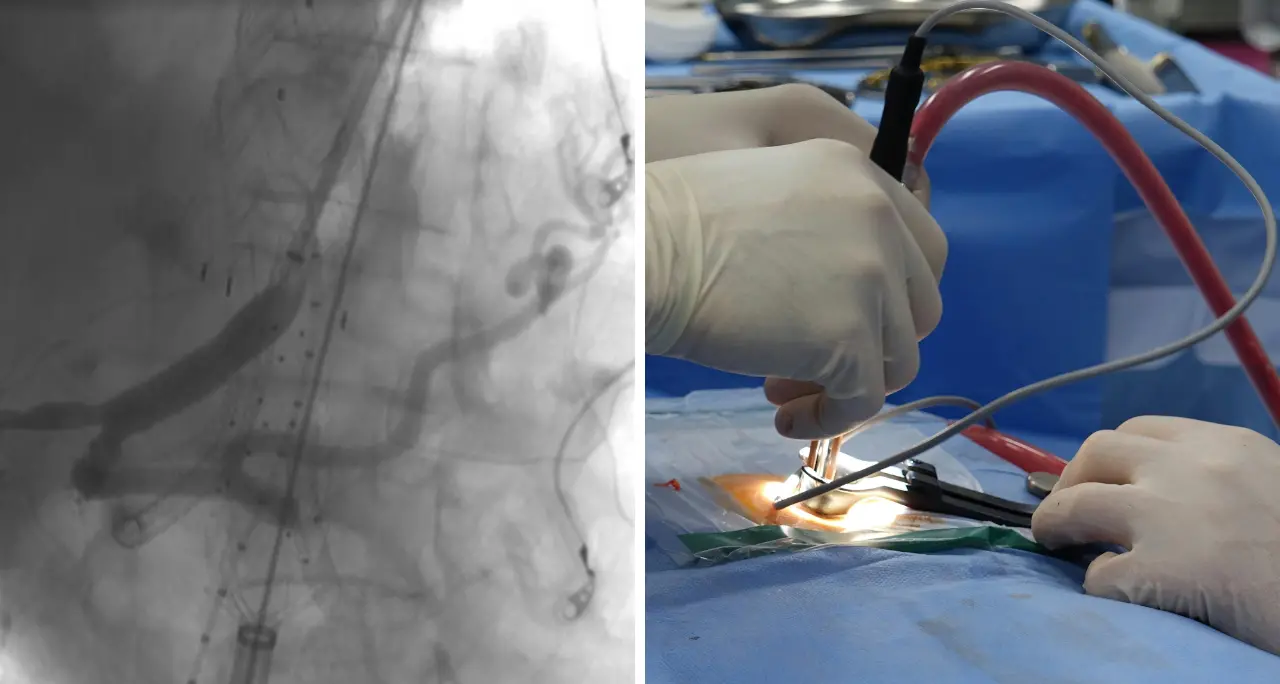

Innovativo intervento all’Annunziata di Cosenza: impiantati due pacemaker senza fili in una paziente con blocco cardiaco

Dall'ospedale bruzio la definiscono «una tappa importante per la cardiologia calabrese». Grazie alle nuove tecnologie è stato possibile intervenire su una donna di 84 anni giunta in Pronto soccorso a seguito di una perdita di sensi improvvisa